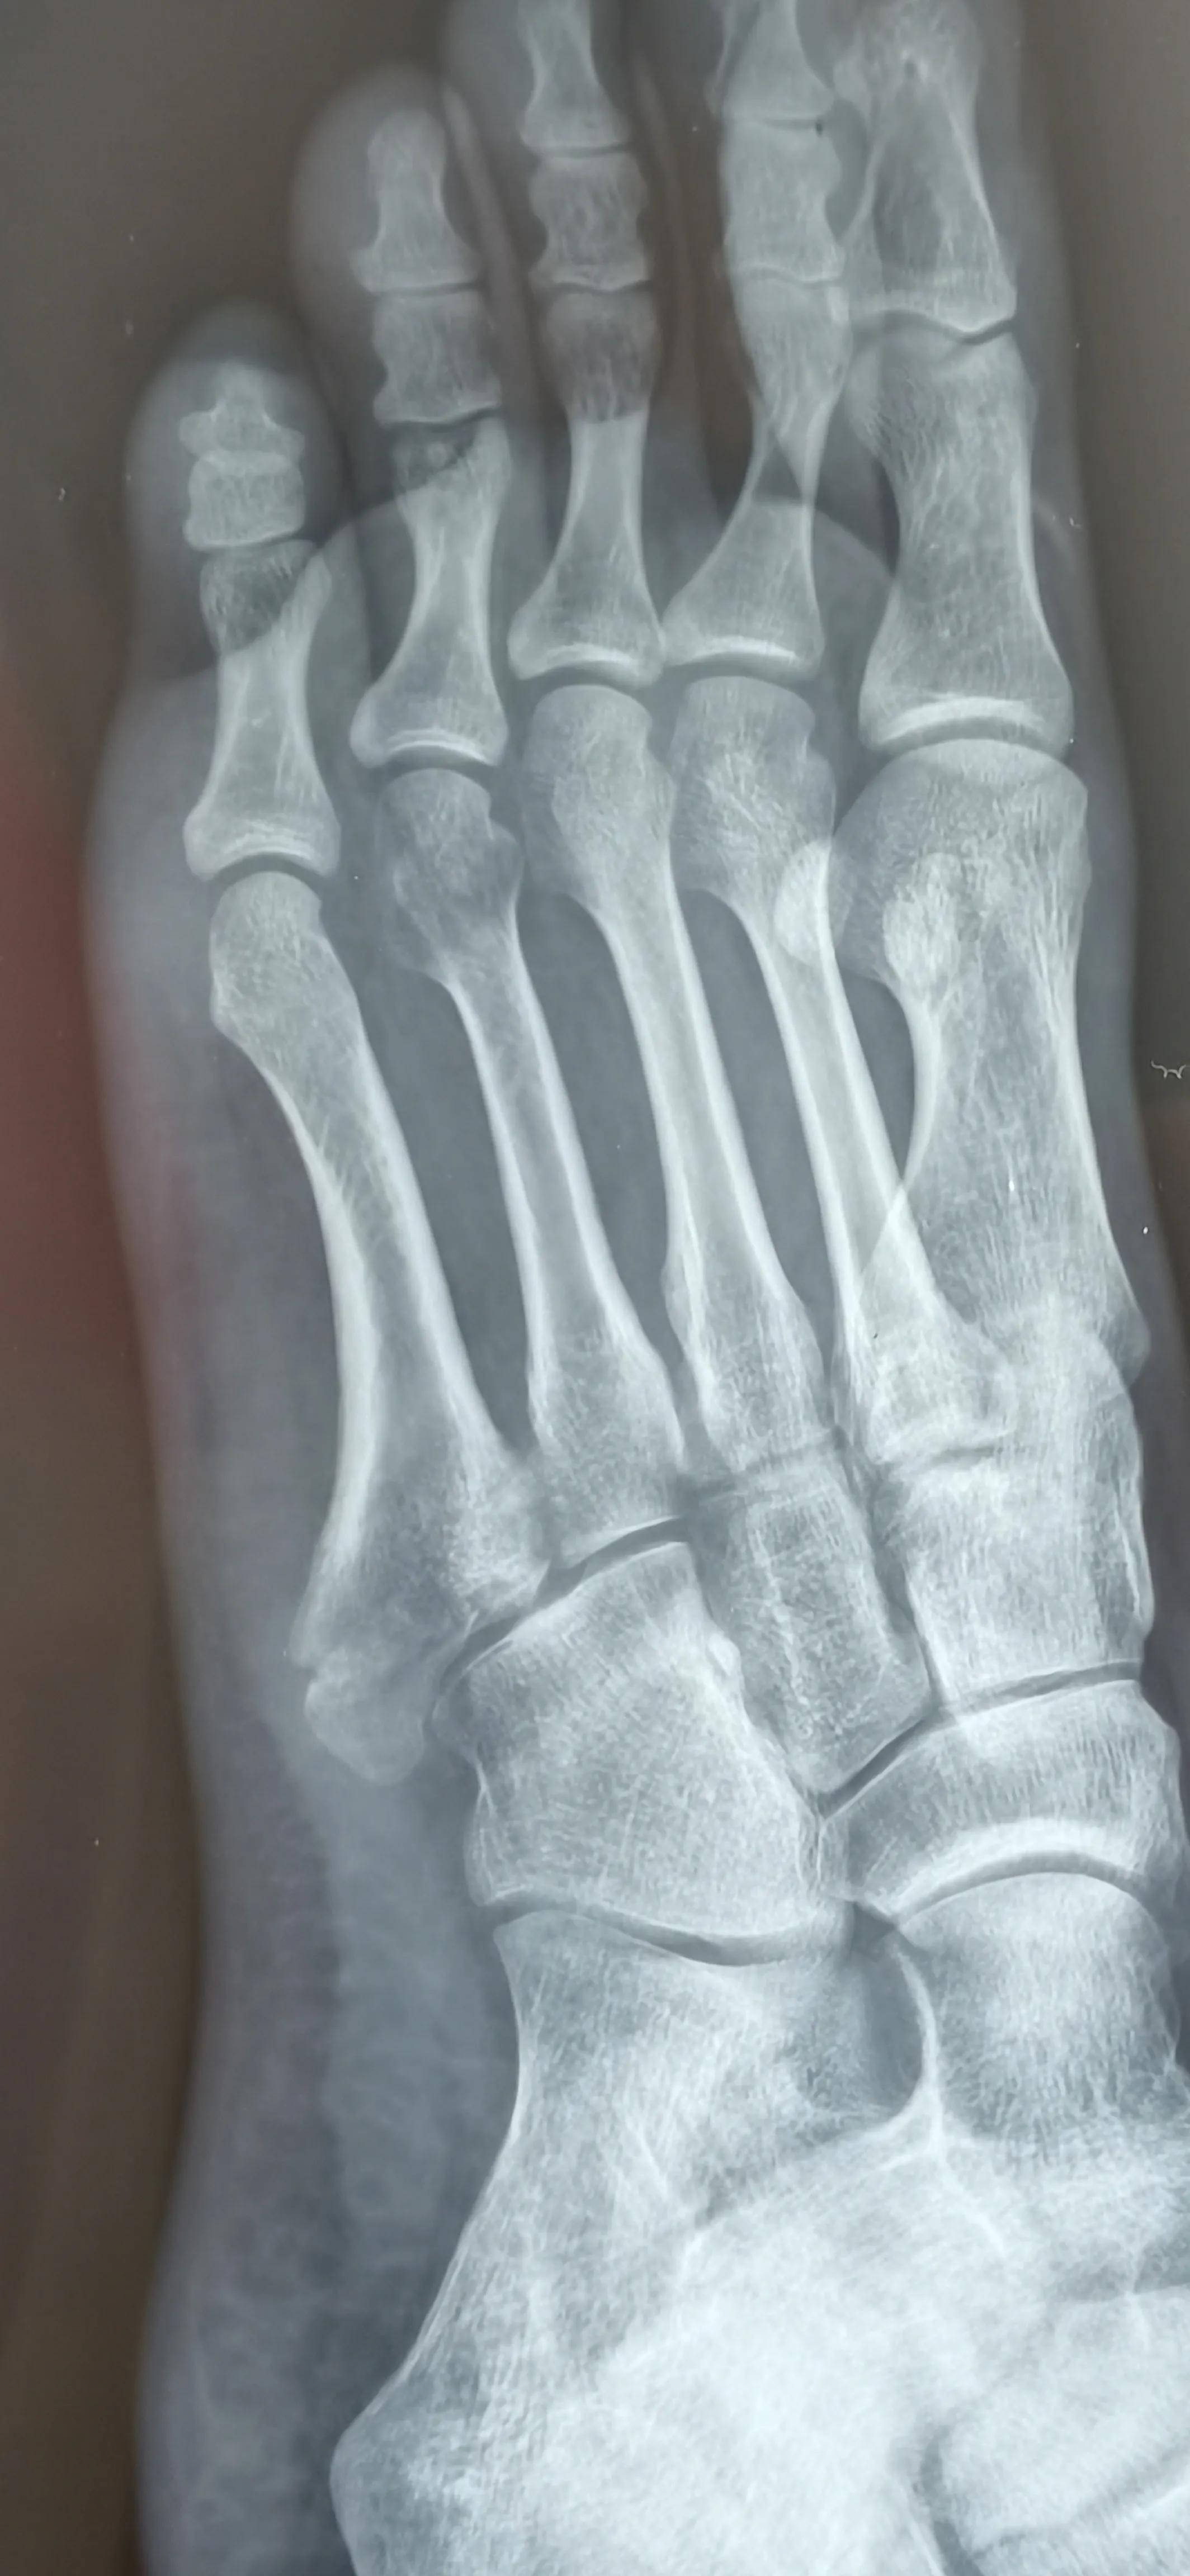

看片子骨缝比较大了,有点移位,而且中间崩碎了一块,一直找不到,后来复查才发现那个碎片掉落在骨缝当中了

此图可以看见中间碎片在骨缝里面

6月底复查,骨缝小的地方已经有了一点愈合的痕迹,医生说如果手术可以在红线位置打个钉子,但是现在打会破坏内部已经开始愈合的部分,建议继续保守……